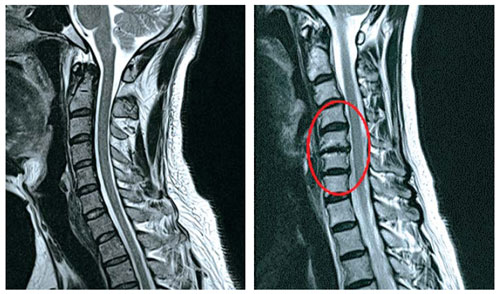

목디스크란 목뼈 사이에 있는 디스크가 손상되어 신경을 압박하는 질환을 의미합니다. 디스크는 젤리와 같은 수핵과 섬유륜으로 구성되어 있습니다. 섬유륜이 손상되면 수핵이 밖으로 밀려나와 신경을 압박하게 됩니다.

목디스크는 주로 잘못된 자세, 과도한 스트레스, 외상 등으로 발생합니다. 잘못된 자세로 장시간 컴퓨터를 사용하거나 운전을 하면 목에 무리가 가고 디스크가 손상될 수 있습니다.

또한 과도한 스트레스는 근육을 긴장시켜 디스크에 손상을 줄 수 있습니다. 외상은 교통사고, 운동 중 충격 등으로 목뼈가 부러지거나 골절되면 디스크가 손상될 수 있습니다.